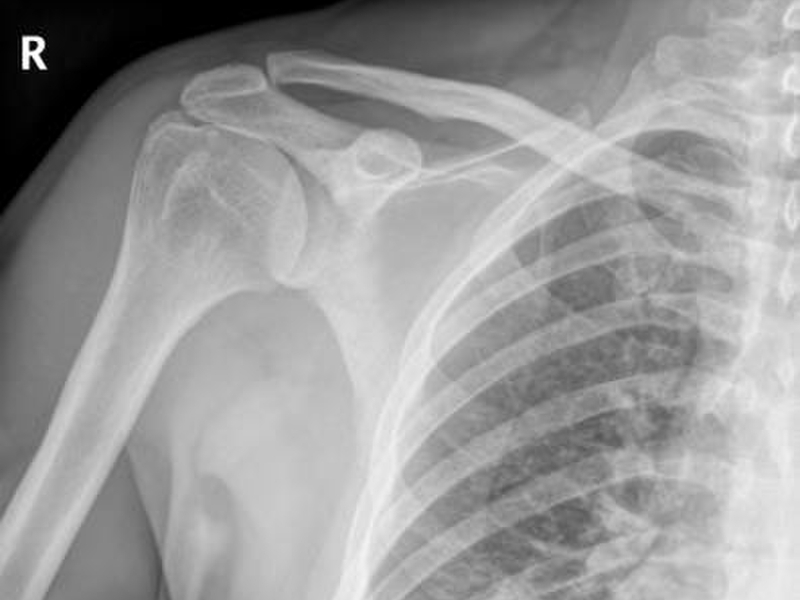

Theo như thường lệ, người bị trật khớp cùng đòn trước khi điều trị sẽ được chụp X - quang khớp vai sau và trước, chụp nghiêng phần tiếp tuyến với khớp cùng đòn khoảng 10 - 15o, theo tư thế chữ Y - Y Scappular view đủ để chẩn đoán xác định và phân loại.

Tuy vậy, trên lâm sàng nghi ngờ trật cùng đòn mà trên X - quang, thông thường sẽ không gây tổn thương thì cần chụp lại khi bệnh nhân cầm vật nặng trên tay để đánh giá khớp cùng đòn khi không cầm nắm vật nặng và so sánh với bên lành.

Người bị trật khớp cùng đòn trước khi điều trị sẽ được chụp X - quang để chẩn đoán

Các đặc điểm trên X - quang: Rộng khớp cùng đòn từ 5 - 8 mm, phù nề phần mềm, không cân xứng với bên đối diện từ 2 - 4mm. Chụp CT và MRI hiếm khi chỉ định. Trường hợp chỉ định nếu thông qua X - quang và lâm sàng không có khả năng chẩn đoán hoặc có các tổn thương khác như (rách chóp xoay, mất vững khớp vai,...)